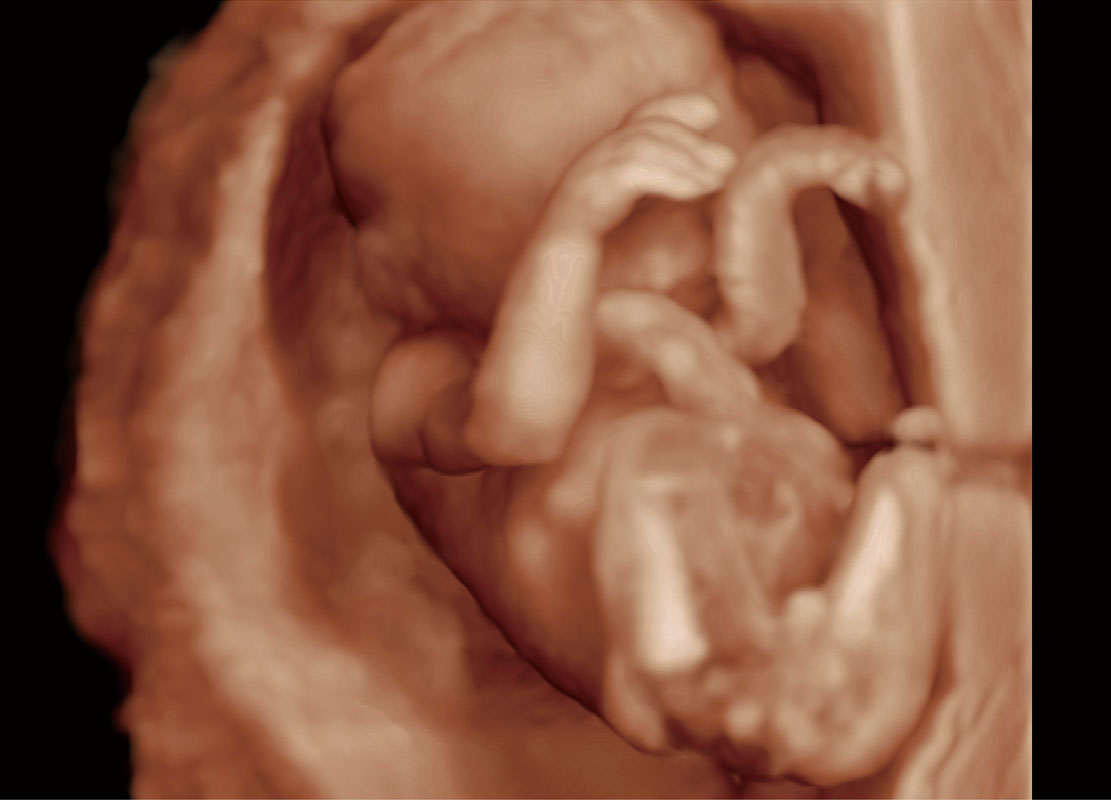

P60在胎兒早孕期超聲篩查中為您帶來優(yōu)異的圖像質(zhì)量。

高分辨率容積成像-早孕胎兒